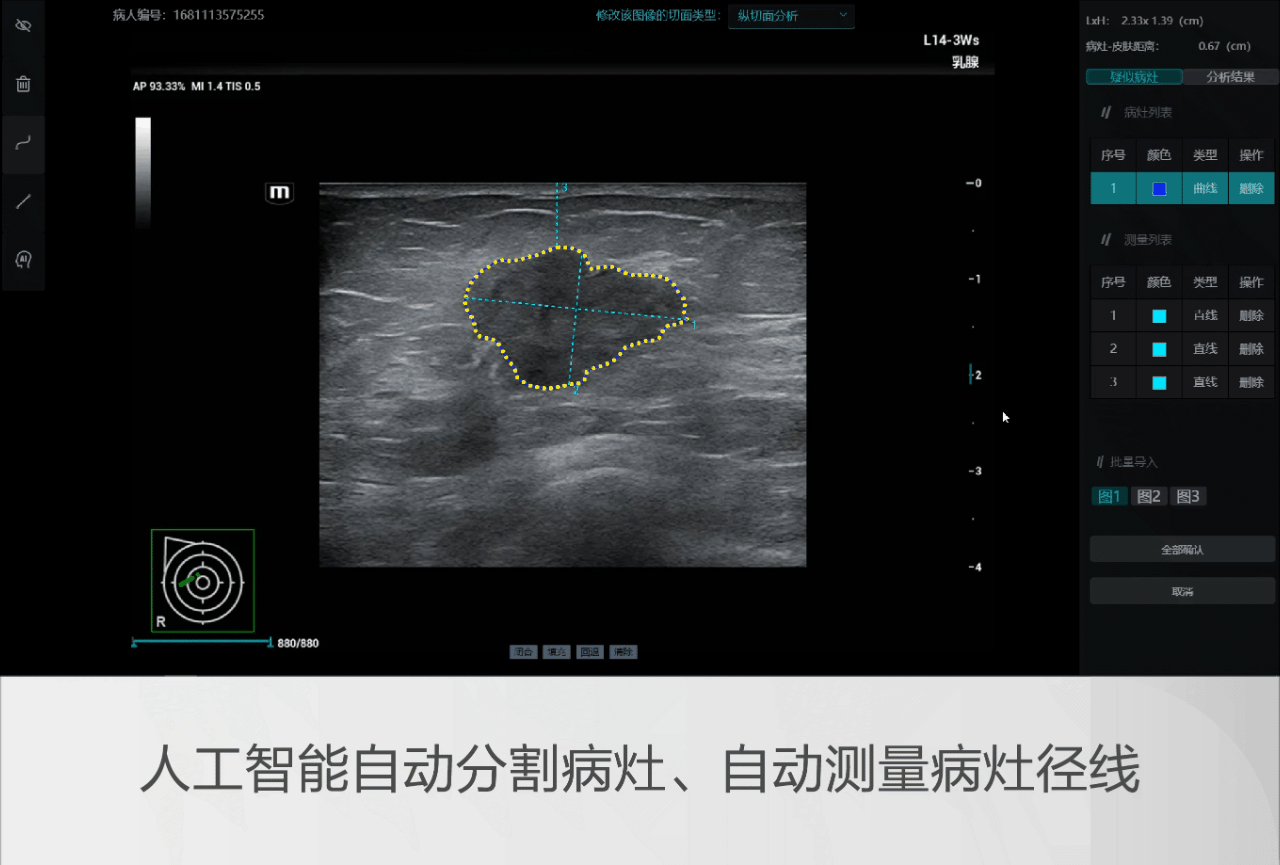

基于人工智能技术,该产品是国内乳腺超声领域首个进入三类创新医疗器械特别审查程序的AI辅助诊断产品。通过规范化智能流程,产品实现乳腺病灶多切面的精准BI-RADS评估与分级(2类、3类、4A类、4B类、4C类、5类),提升乳腺癌早期诊断精度,助推医疗均质化发展。

为了应对这一挑战,迈瑞以《乳腺疾病超声检查质量控制专家共识(2019版)》为基准,以覆盖实际临床场景的图像与专家组诊断结果,作为训练数据及金标准,通过创新的深度学习算法,将临床知识与高年资医生对图像判读的经验融入辅助诊断模型中,即使面对复杂病变,软件也可以给出高效精准的临床分类诊断。

以临床为导向,迈瑞乳腺超声辅助评估软件具以下创新优势:不改变诊疗操作习惯的多切面综合分析;全自动化分析流程,图像导入后无需人工干预,可以直接得到分析结果;BI-RADS六分类诊断(2类、3类、4A类、4B类、4C类、5类)、BI-RADS特征都能给出对应且明确的结果。

在临床验证中,迈瑞乳腺超声辅助诊断软件与高年资医生判读结果高度一致,且软件为低年资医生的诊断准确性带来显著提高。